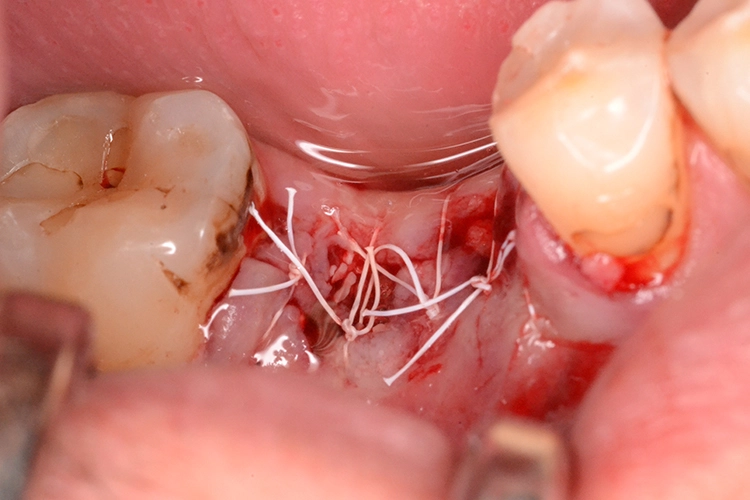

4. Sofortimplantation im Molarengebiet

Dr. Opitz

Aufgrund der Augmentation erfolgte die Freilegung 5 Monate postoperativ. Nach Ausformung des Emergenzprofils (Abb. 4i) erfolgte die definitive prothetische Versorgung durch eine okklusal verschraubte Einzelkrone (Abb. 4j).